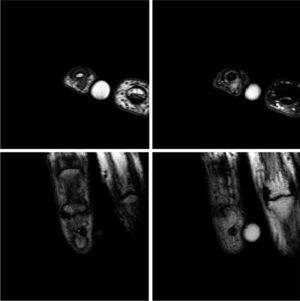

El estudio con RM objetiva un nódulo en el pulpejo del meñique, a la altura de la porción central de la falange distal y sin aparente relación con la articulación interfalángica. Se muestra bien delimitado y de 4mm de diámetro. Destaca la hiperintensidad de señal en las secuencias potenciadas en T2, sugiriendo el diagnóstico de tumor glómico (fig. 1).

Estudio RM de la lesión. Arriba: cortes axiales, secuencias T1 TSE y T2 SPAIR, respectivamente. Abajo: cortes coronales, secuencias T1 TSE. Se observa un nódulo situado en el pulpejo del dedo, a la altura de la porción central de la falange distal y sin aparente relación con la articulación interfalángica. Este nódulo está bien delimitado y mide 3mm de diámetro.